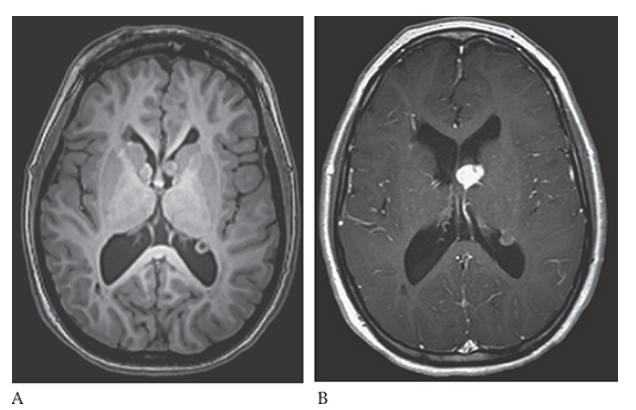

What is A

Glioblastoma Multiforme. shows an isointense mass with low-signal central necrosis and surrounding edema. Postcontrast T1W image

What is B

Glioblastoma Multiforme.hows peripheral irregular enhancement. FLAIR image